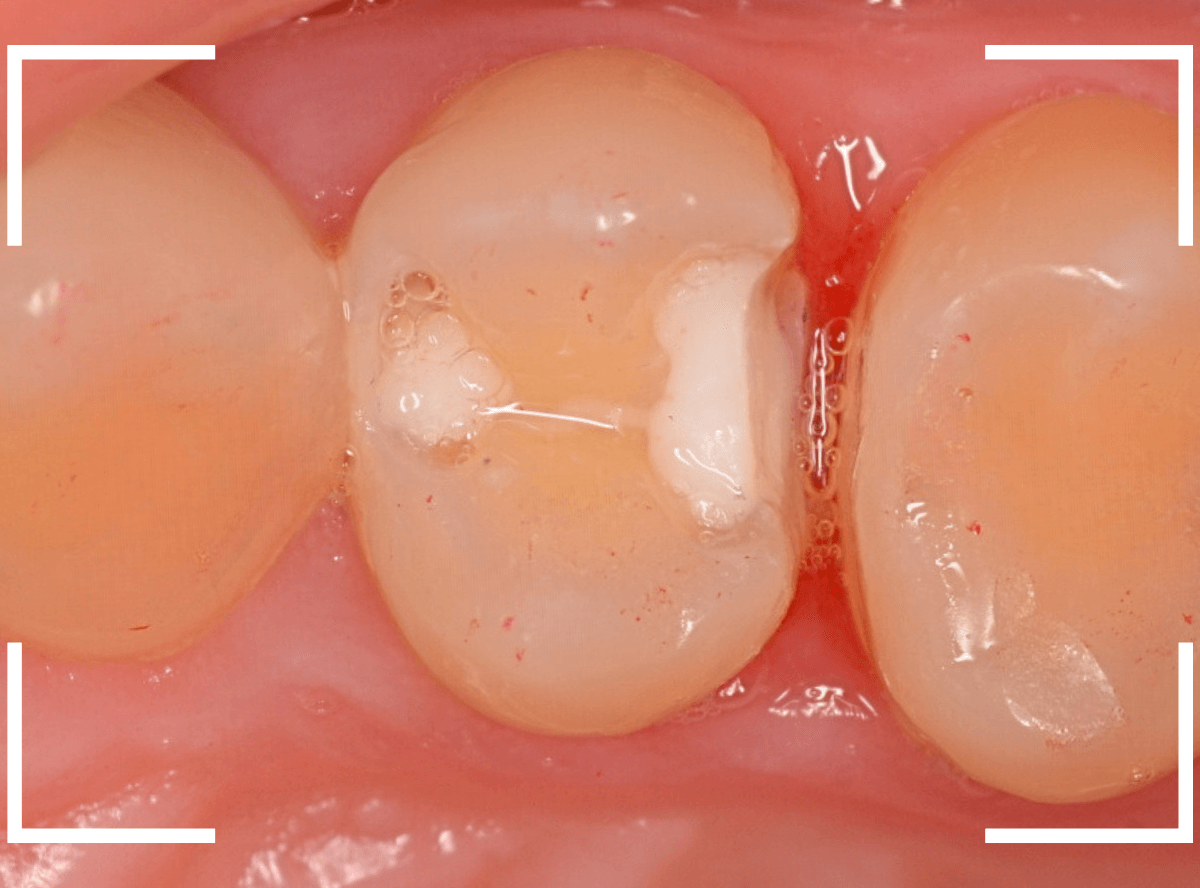

Case.24 レジンの下で虫歯が進行

上の奥歯の虫歯が見つかった患者さんです。

初診のチェックの際に、上から目視すると、レジンがつめてある〇部分が薄暗く黒くなっているので、これは虫歯があるな、とわかりました。

レントゲン写真で確認します。

赤いラインが虫歯と思われる部分、青いラインが歯の神経です。

先ほどの〇部分は明らかな虫歯になっているのがわかります。

この辺りはレジンがつめてありますが、その下もうっすらと虫歯になっていそうです。

治療を開始します。

先ほどの黒く見えた部分は少し削るとすぐに虫歯が出てきました。

手前の歯まで虫歯を除去した時点で、う蝕検知液で確認します。

赤く染色されている部分が虫歯です。

思ったよりも深めの虫歯ですね。

レジンを除去して虫歯をすべて治療したところです。

レジンの中も全体にうっすらと虫歯になっていました。

このくらいの虫歯でも、患者さんは自覚症状はありませんでした。

ご自身の自覚症状だけでは、虫歯の状況がわからないですし、自然に虫歯が治る事もありません。

いつものお話ですが、定期的なメンテナンスで、虫歯の早期発見・治療を心がけましょう。